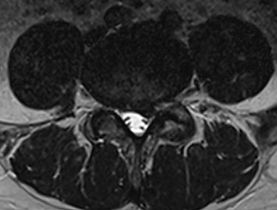

Jostas daļas diska trūce

L4-5 jostas daļas diska trūces piemērs magnētiskās rezonanses izmeklējumā.

Liela diska trūce 3 x 1.5 cm